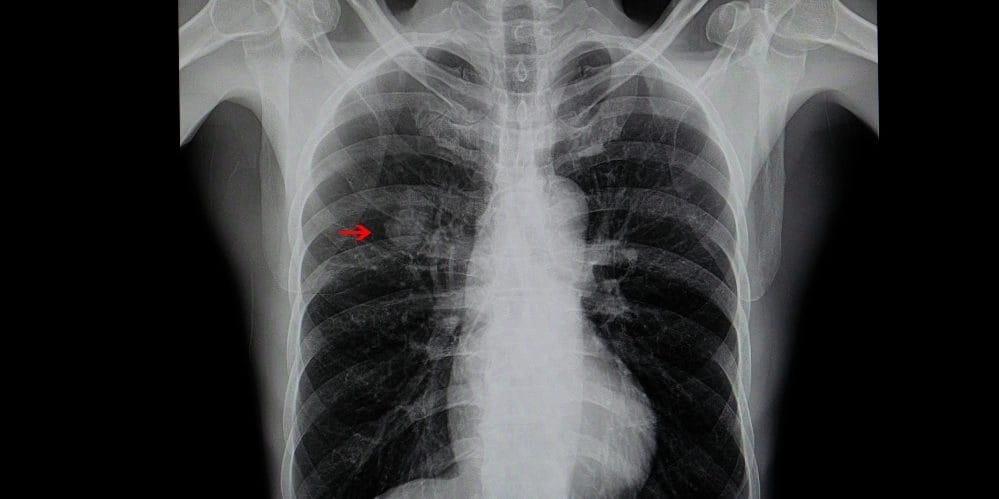

| Болезни легочной системы | Наличие и характер кашля, выделение мокроты, показатели температуры тела | Рентген органов грудной клетки, флюорография |

- Флюорографию.

- Рентген грудины.

Если такие опасные для жизни заболевания, как инфаркт, туберкулез или плеврит не подтвердились, можно приступать к дальнейшему обследованию. Сразу после лечащий врач назначает пациенту магнитно-резонансную томографию. Она позволит определить, страдает ли человек остеохондрозом, торакалгией или межреберной невралгией. После проведения первичной диагностики, терапевт направляет пациента уже к более узкому специалисту — кардиологу, неврологу и прочим.